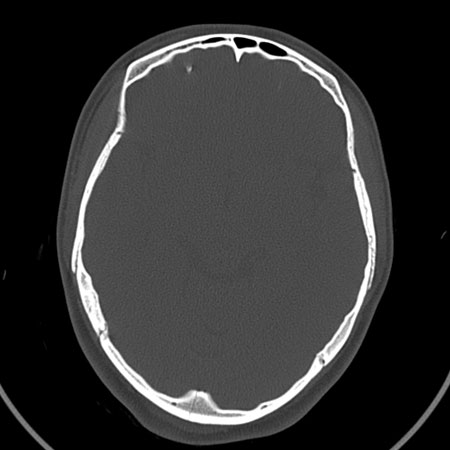

请问各位战友:图示箭头处是否为颅骨骨折?

病史:患者,女,20岁.头部及腹部外伤20分钟.伤后昏迷,无呕吐.头及右侧腰背部疼痛,双侧瞳孔等大,

右肾区叩痛.其它无异常.患者家属否认原有外伤史.

请大家看看是否为颅骨骨折.还是正常变异,或为陈旧骨折.谢谢.

图片未上传完,所见图象示枕骨线样低密度影,边缘锐利,结合外伤史,伤后昏迷,骨折不能除外。

枕骨的线样低密度影锐利、清晰,但正好位于矢状缝的位置,局部无明显软组织肿块,相临及对冲部位脑实质亦无出血及挫裂伤表现。

单就这几层暂不考虑骨折,建议上传完整图片。

楼主所关心的另一个线样影应该是头颅矢状面略偏左,射线正好穿过所致,不需要考虑骨折。

枕骨是单块的,矢状缝是在顶骨而不是在枕骨,枕骨后缘见线状低密度,边缘税利,考虑在骨折存在。

枕后部及左侧颞枕部边缘锐利的线样低密度影,局部软组织无异常,左侧乳突蜂房密度均匀,硬膜下及脑实质内未见出血灶,考虑为正常变异。

枕部考虑骨折。一般的颅逢不会跨越板障,楼主所示枕骨断面两侧板障也不连续。